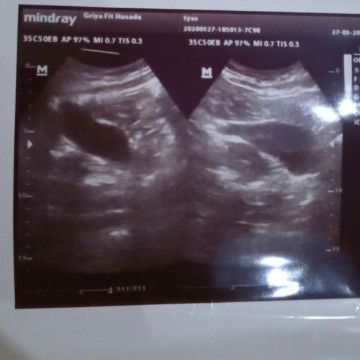

Usg

Bun mau tanya jika.hasil usg seperti ini, apakah saya beneran hamil.... Mf bun nanya2 soalnya ini baru prtama ?